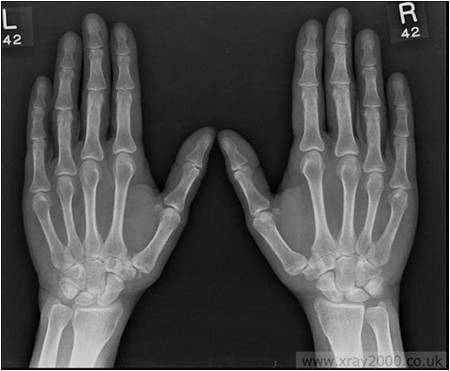

Figure 1

|

- AP view of X-rays of both hands with wrists

- There is juxta-articular and generalized osteopenia

- Soft-tissue swelling is seen near right ulnar styloid, right fifth MCP and left index, middle PIPs

- There is a significant joint space narrowing in the radiocarpal (L>R), intercarpal (R>L), left thumb MCP, right index MCP, B/L PIPs

- Erosions are well seen in R>L carpus, R index MCP, L Thumb MCP and B/L PIPs